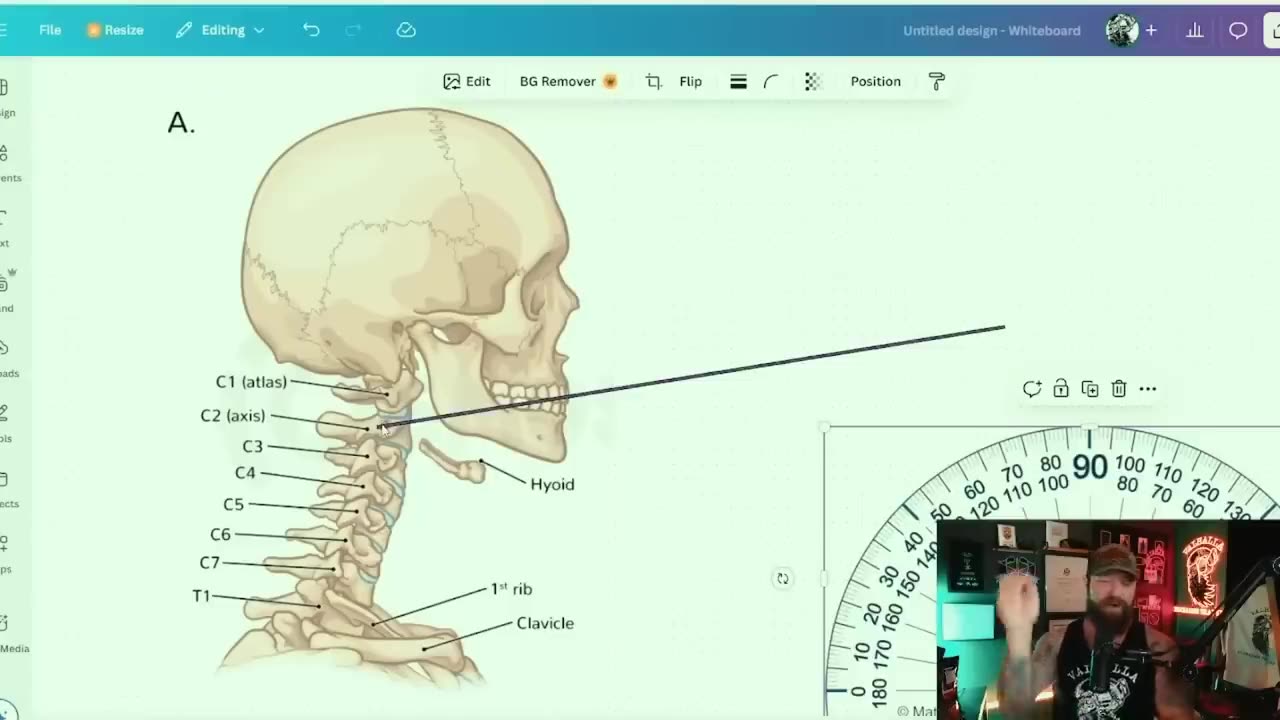

ABOUT ЗІ/ATLAS

December 11, 2025